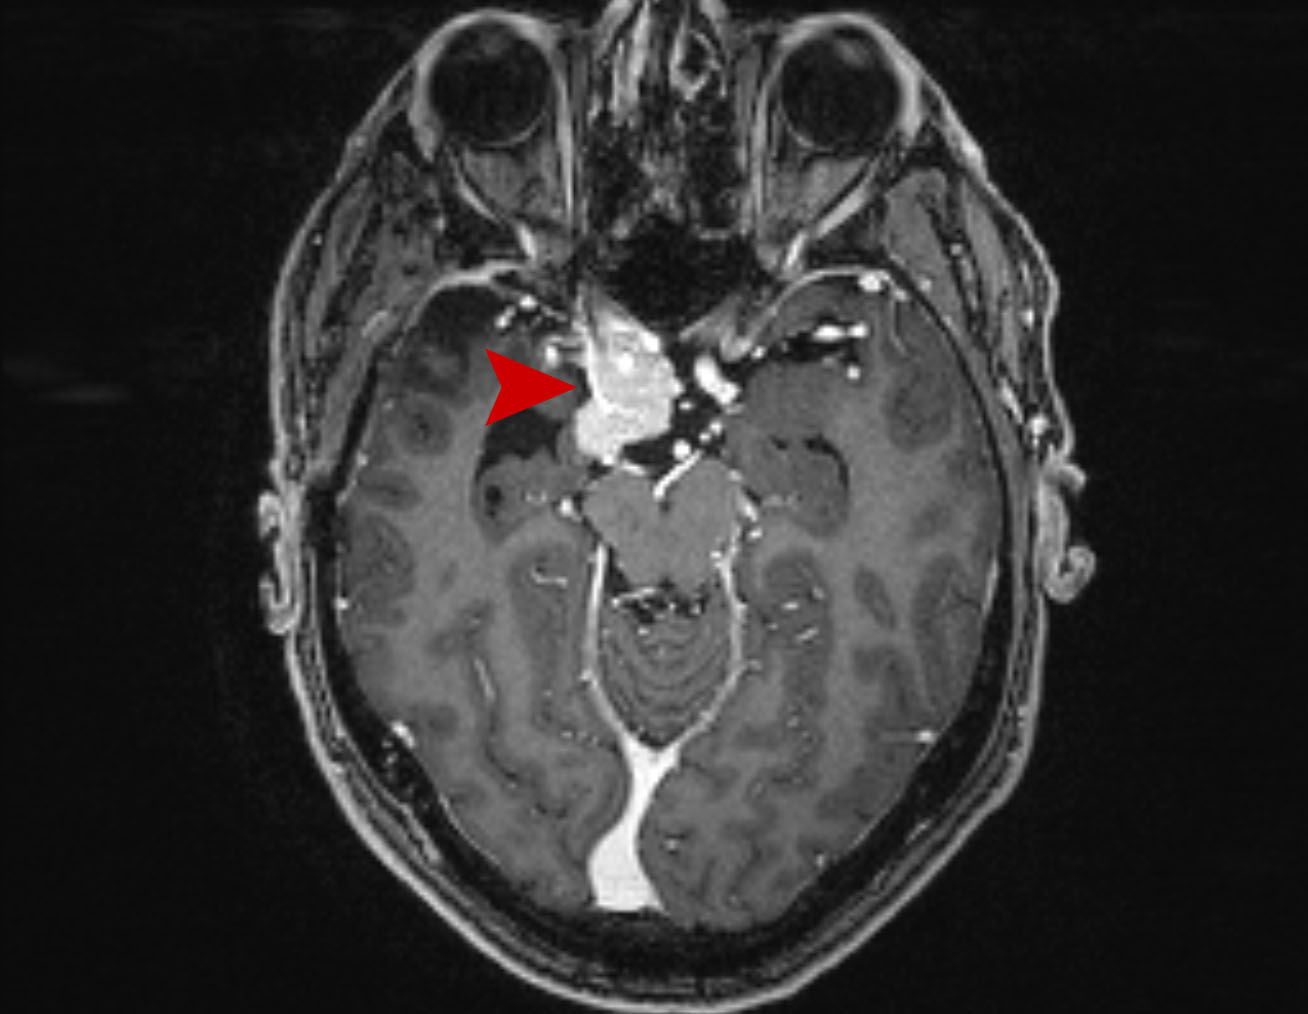

Μεταστατικός Καρκίνος Πνεύμονα στον Εγκέφαλο Θεραπεία με CyberKnife #25

Άρρεν 58 ετών με ευμεγέθη εγκεφαλική μετάσταση από Ca πνεύμονος κατά το αριστερό εγκεφαλικό σκέλος…